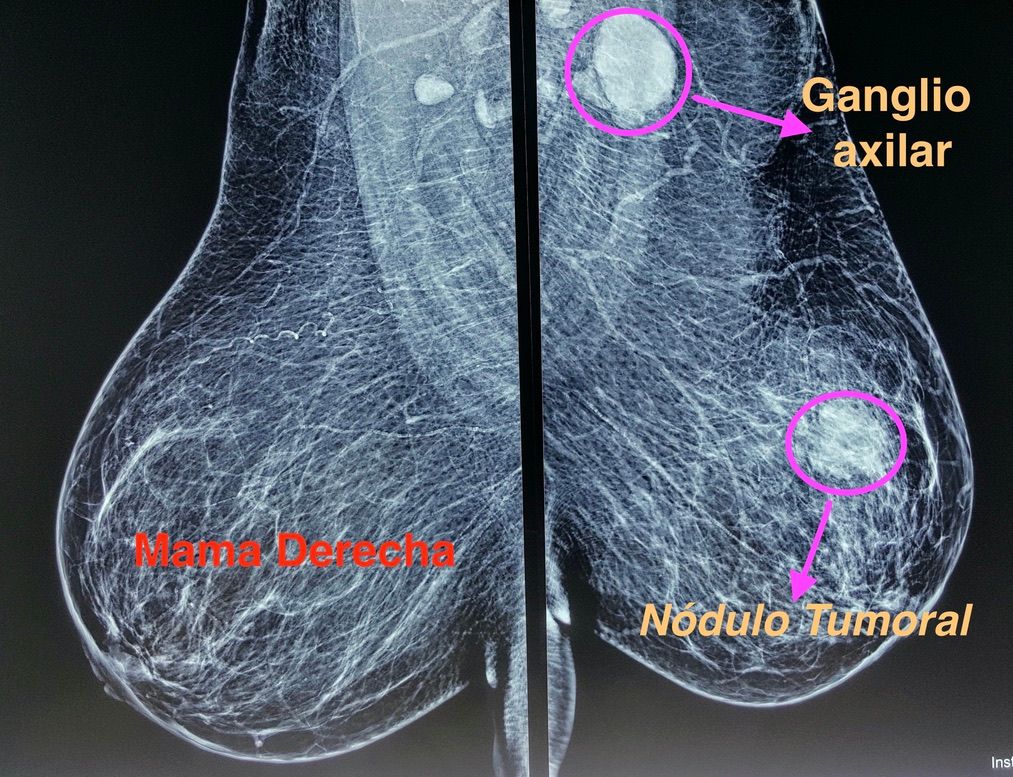

Tumor de mamas

Tumorectomia de mama (Cuadrantectomia)

Tumorectomia de mama con vaciado axilar

Tumores mamarios

Biopsia de mama por marcaje

Biopsia mamaria

Biopsia trucut de mama

Biópsia quirúrgica de mama